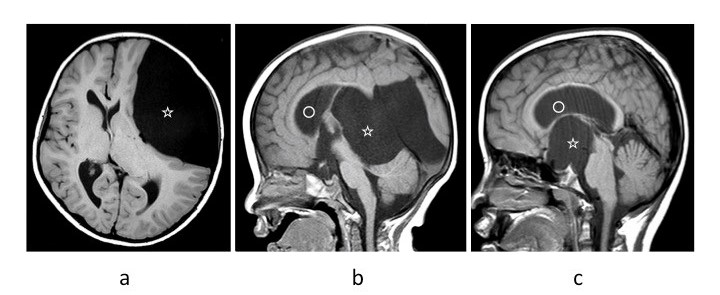

くも膜のう胞のMRI. a; 中頭蓋窩 b; 四丘体部 c; 鞍上部

MRIやCTで診断します。のう胞の大きさや周囲への影響を評価できます。大泉門が閉じていない乳児ではエコーを用いることもあります。